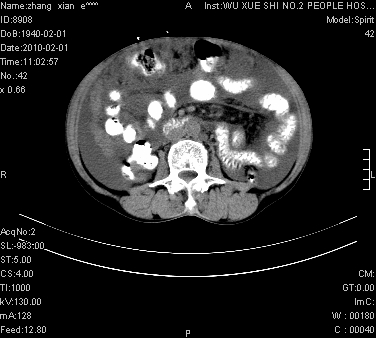

标题: CT24434:70岁 女 腹胀,腹水原因待查 [打印本页]

标题: CT24434:70岁 女 腹胀,腹水原因待查

大量腹水,脾脏囊性占位,子宫颈占位,右侧腹股沟淋巴结肿大,建议+c,先查妇科。

腹盆腔大量积液,子宫增大,子宫颈增大外形不规则,内见低密度影,膀胱后壁显示不清,右腹股沟肿大淋巴结,脾脏囊性占位,子宫颈占位,子宫颈癌?建议增强。

考虑:1、腹膜转移,大量腹水;

2、脾占位性病变;

3、左侧卵巢占位性病变,建议增强进一步检查。